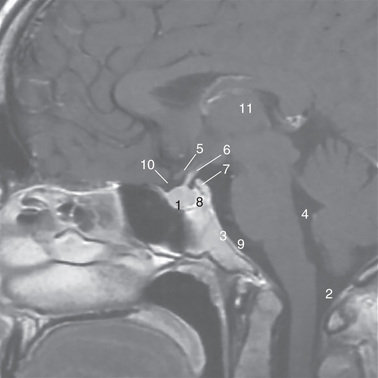

24

Midbrain

32

Pons

23

Medulla oblongata

4

Clivus

What does the brainstem lie on in the occipital bone

4th/fourth ventricle

Floor of fourth ventricle

2

Cisterna magna

Cerebral aqueduct